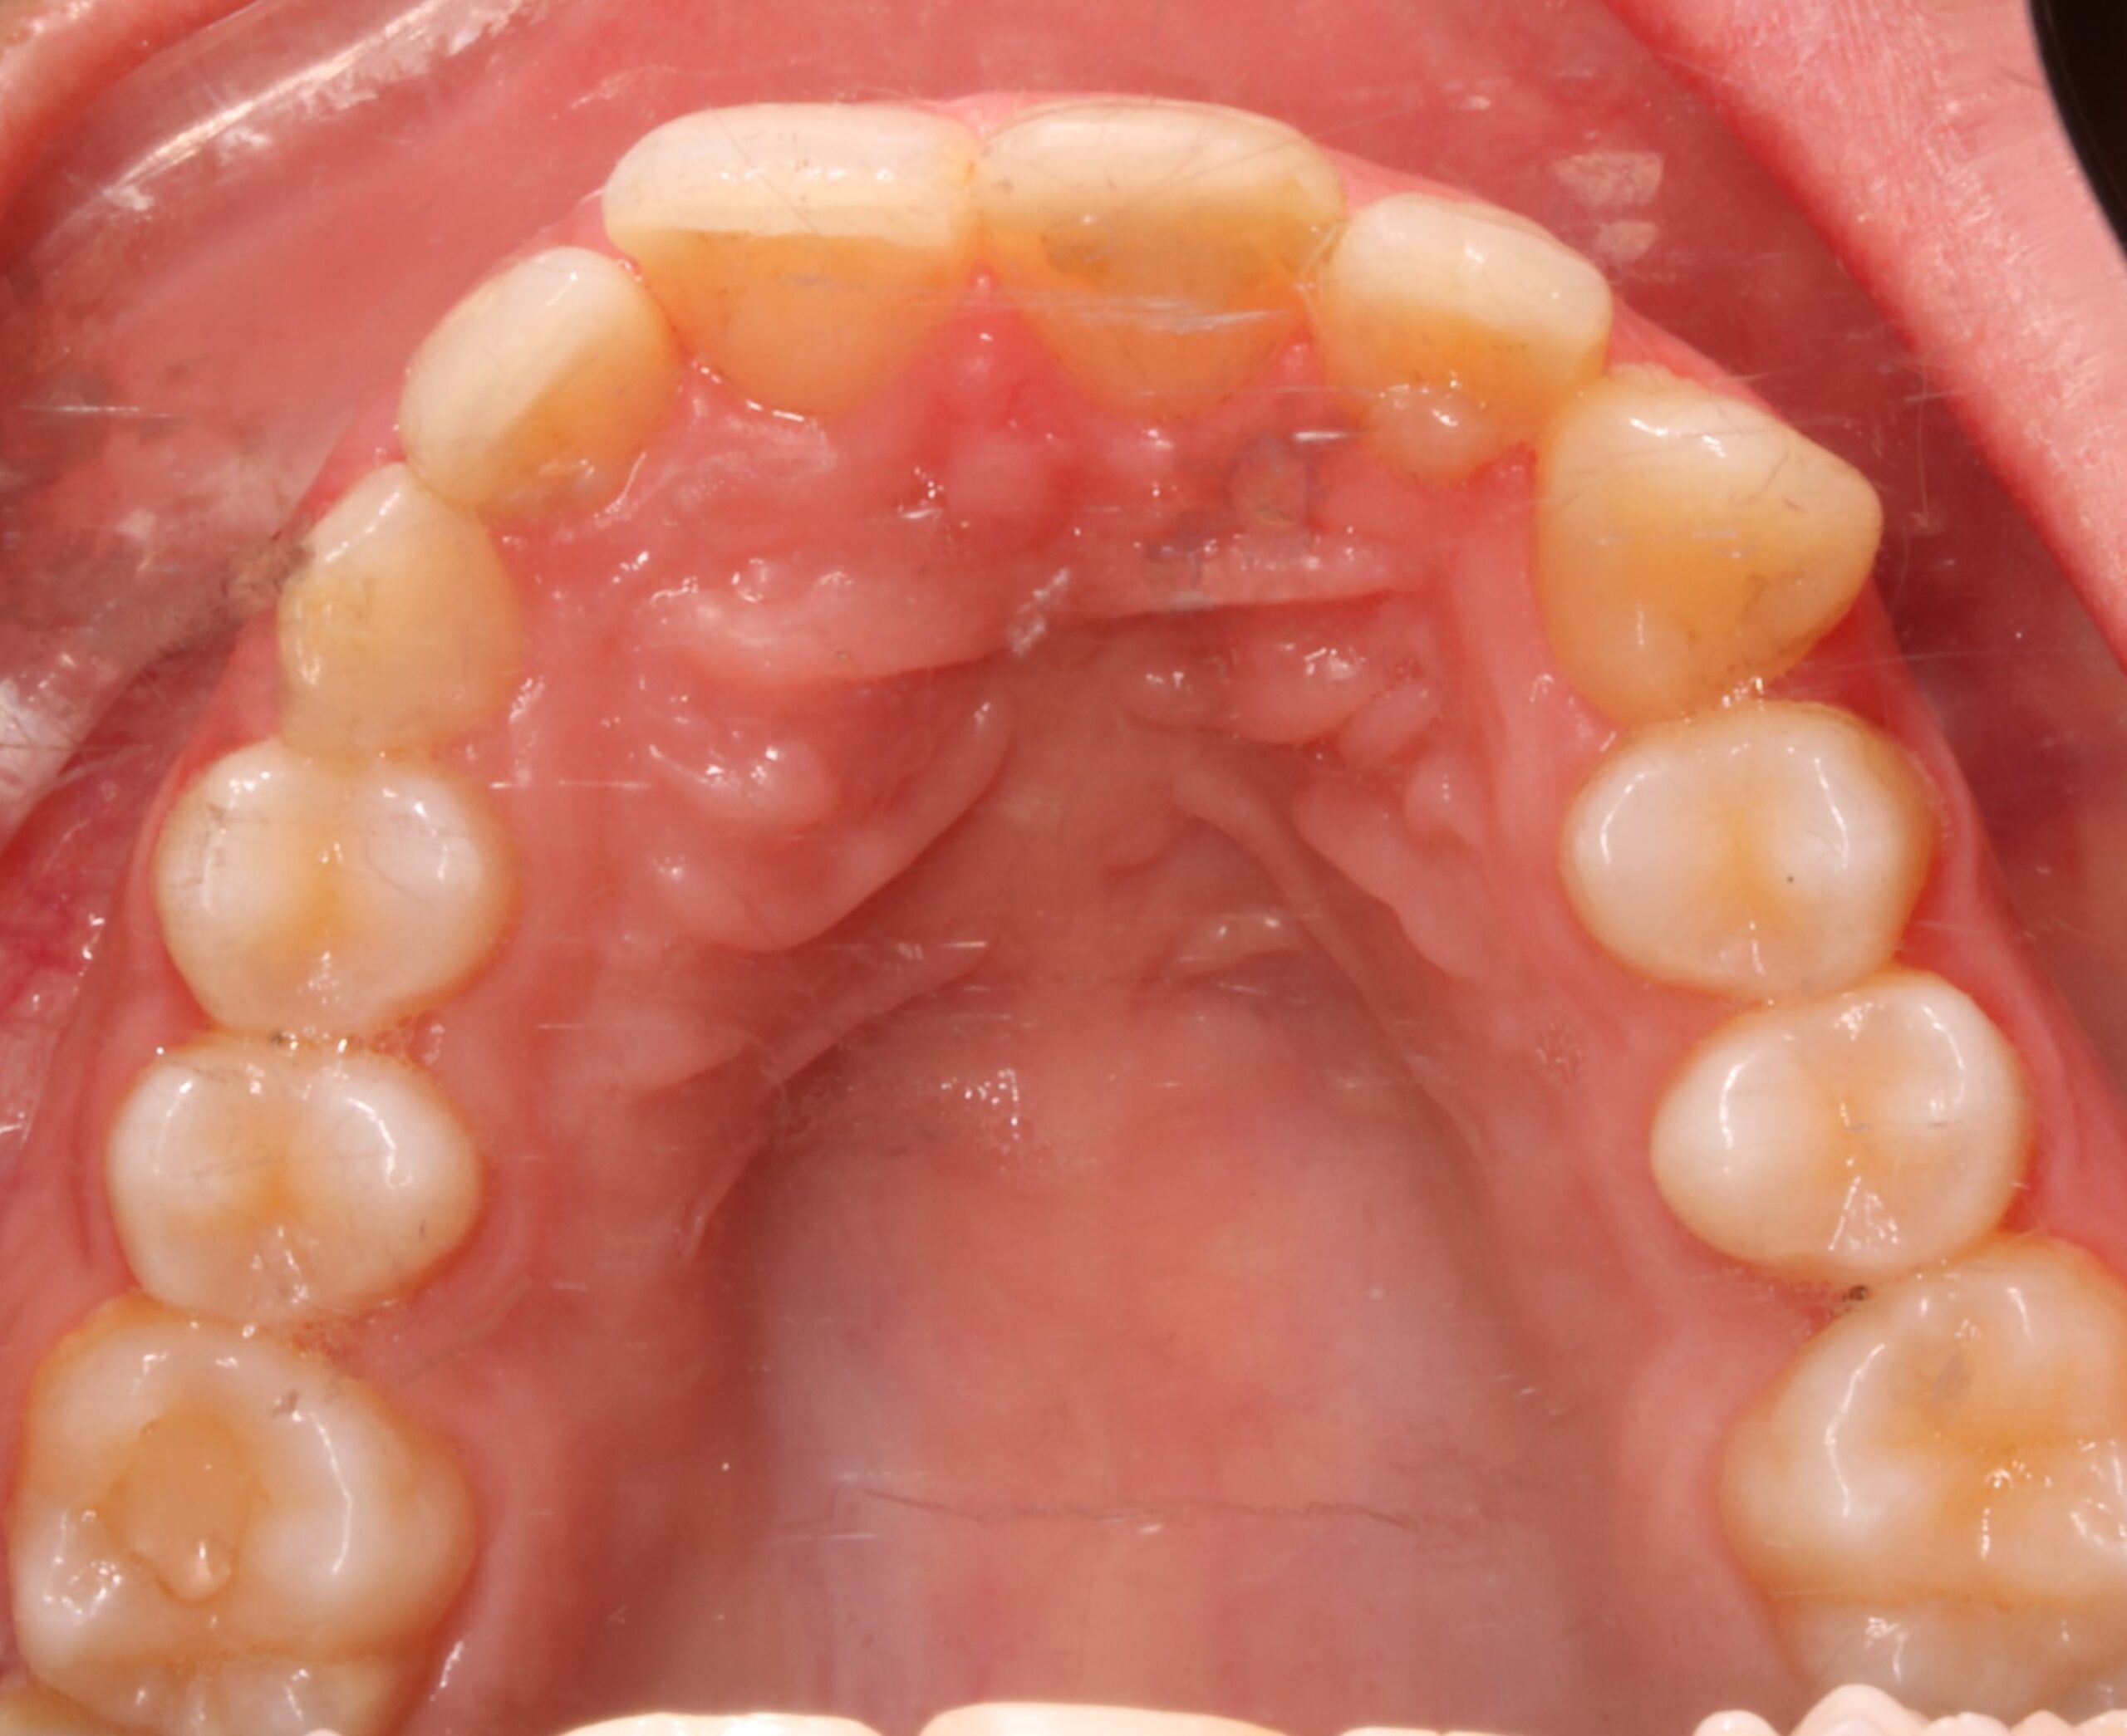

Se muestra el caso de una paciente con un canino incluido en el paladar (pieza 13).

C) ¿Está el canino incluido por palatino asociado a otros posibles hallazgos clínicos? Si. ¿Cuáles?  Disto angulación de los segundos premolares; infra oclusión de dientes temporales; microdoncia de incisivos laterales superiores; agenesia de un incisivo lateral superior o de terceros molares.

-En este caso no se encontraron ninguno de eso hallazgos clínicos frecuentes.

Atendiendo a estos criterios, en nuestro caso, el pronóstico es bueno. Ya que tres de los cuatro criterios son favorables: el ápice se encuentra en una posición ideal, la distancia al plano oclusal no es mayúscula y la inclinación es mayor a 31 grados. Solo la posición de la corona cerca de la línea media aumentaría la dificultad.